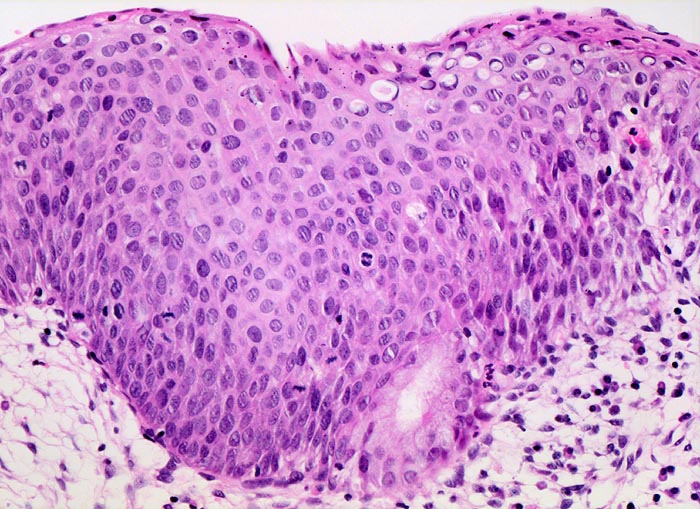

PathoPic – image database / PathoPic ID 3346 - mässige Dysplasie des Plattenepithels, parakeratotische Verhornung

mässige Dysplasie des Plattenepithels, parakeratotische Verhornung

Portio

Metaplastisches Plattenepithel der Portio. Vergrösserte leicht hyperchromatische Kerne und Mitosen bis auf halbe Epithelhöhe. Weitgehend erhaltene Architektur. Entzündungsinfiltrat im Stroma.

Pap IV, rezidivierend. Konisation

200

26